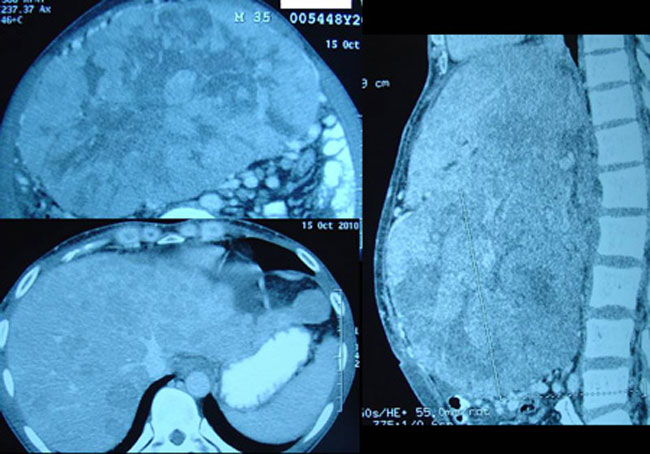

Not knowing what else to do, Goh and his family came to seek our advice on 24 October 2010. His CT scan report dated 15 October 2010 stated: “Both lobes of liver are enlarged and studded with multiple ill-defined heterogeneously enhancing lesions. The largest lesion located in segment 4b measures 15 x 20 x 15.6 cm. Impression: Multicentric hepatoma with minimal ascites and dilated left intrahepatic duct.”